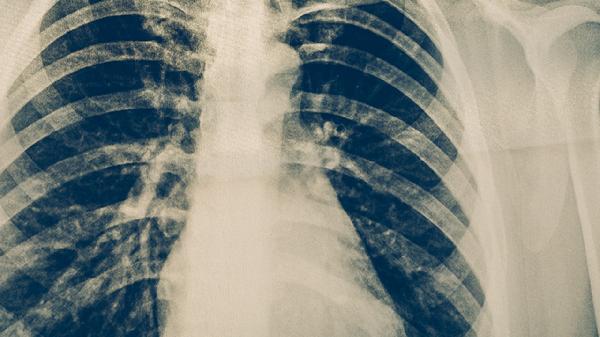

复方万年青胶囊主要成分包含虎眼万年青、白花蛇舌草等中药材,具有解毒消肿、散结止痛功效,说明书标注可用于辅助治疗肝癌、胃癌等消化道肿瘤。但肺癌的病理类型、分期及治疗方案与消化道肿瘤存在显著差异,目前缺乏明确循证医学证据支持其对肺癌的疗效。肿瘤患者使用中成药需考虑药物相互作用,例如该药可能影响靶向药物代谢或加重放化疗引起的肝损伤。